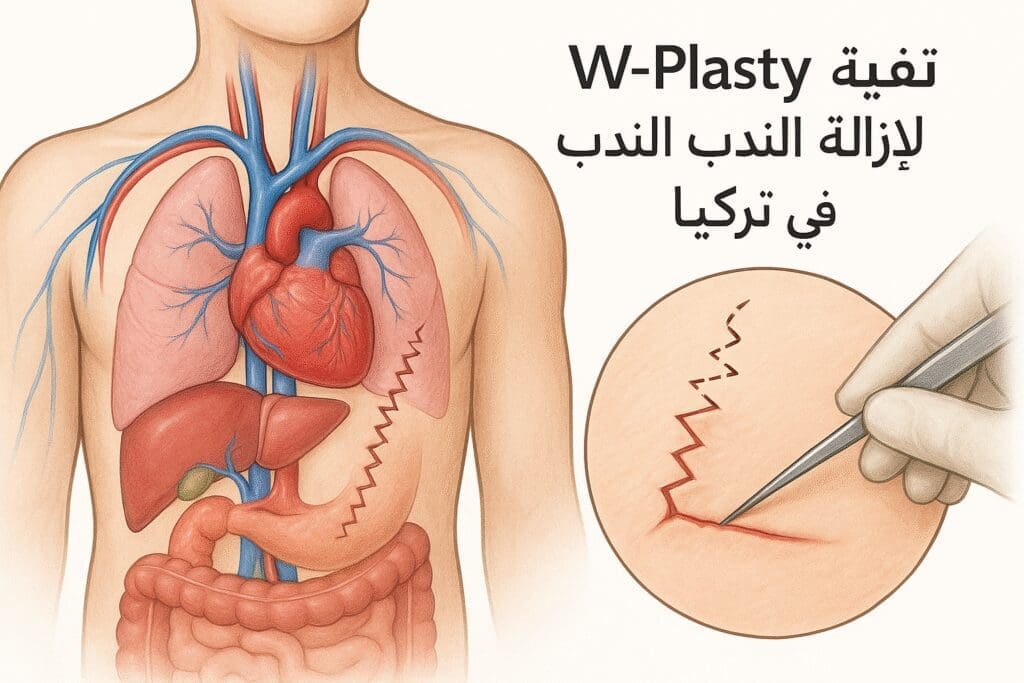

مقالات طبية من مساهمات الأطباء